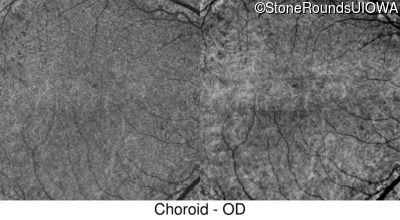

Swept-Source OCT - Right - 20/40 +2 sc

Exemplar